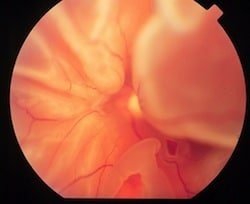

Figura 5. Desprendimiento de retina por necrosis retinal aguda ya reparado con impactos recientes de laser y aceite de silicón.